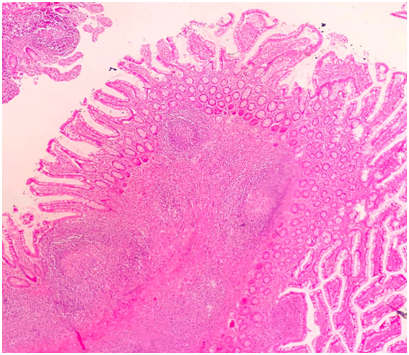

The pathology result of the specimen was reported as right hemicolectomy, phlegmonous appendicitis, localize peritonitis, abscess formation and reactive lymph nodes. Diagnosis of actinomycosis of the appendix was established histologically. Typical histologically, the microorganism forms actinomycotic granules (sulfur granules) and these are made of relatively round bacterial aggregations surrounded by eosinophilic material. Microscopic examination of our case revealed acute phlegmonous appendicitis, peritonitis and actinomyces sulfur granules scattered in the purulent exudate in the appendiceal lumen (hematoxylin and eosin (H&E), ×2 magnification) (Figure 2-5).

Figure 4Phlegmonous appendicitis consisting of neutrophilic infiltration in the appendix wall and serosa.